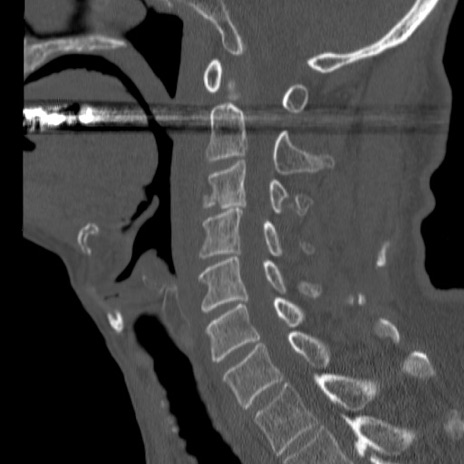

症例46 頚椎CT(矢状断像)

【症例】80歳代男性

【主訴】両側頚部〜上肢のしびれ

【現病歴】昨日、自宅内で転倒、その後より上記症状あり。意識障害なし。

【身体所見】両側上肢のallodynia(熱痛覚過敏)あり。MMTおよびDTRは正確な所見取れず。両上肢の挙上はなんとか可能。

異常所見と診断は?